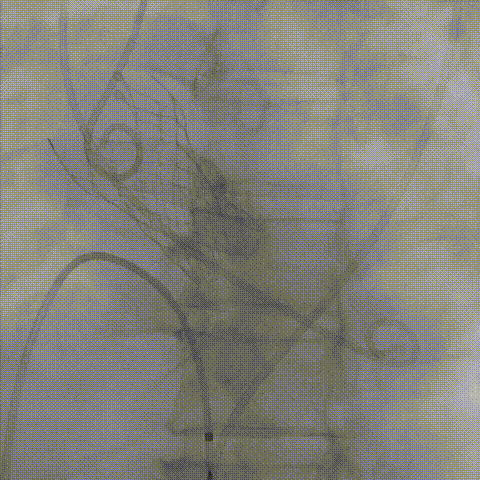

根部造影